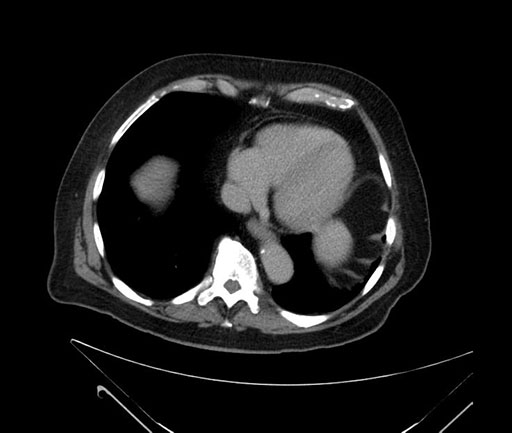

Whipple (pancreaticoduodenectomy) [case 7]

Imaging Analysis

Look through the patient's CT scan to identify any areas of concern for the necessary procedure.

Axial - stented